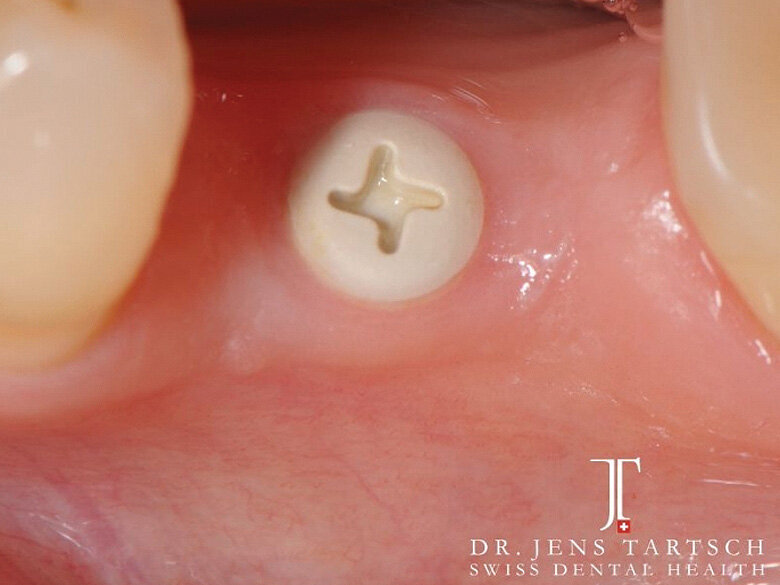

Fig. 7: Healing period with healing cap ZERAMEX XT. (Photo: Jens Tartsch, DMD)

Fig. 8: ZERAMEX XT implant ready for impression. (Photo: Jens Tartsch, DMD)